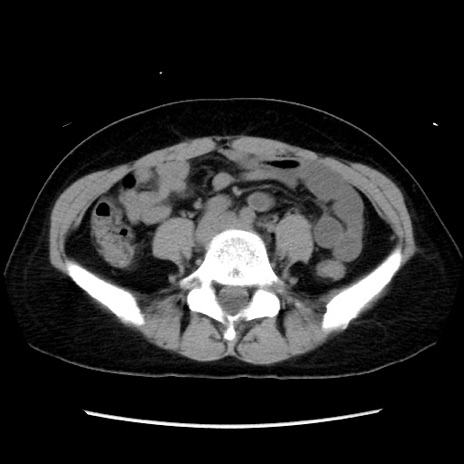

症例10(横断像)

【症例】 50歳代女性

【主訴】 腹痛

【現病歴】前日生レバーを食べた。今朝に排便あり。 昼前に突然発症の腹痛を生じ、当院救急外来を受診した。

【身体所見】 意識清明、腹部:平坦、軟、下腹部やや左を中心に圧痛・反跳痛あり、筋性防御あり